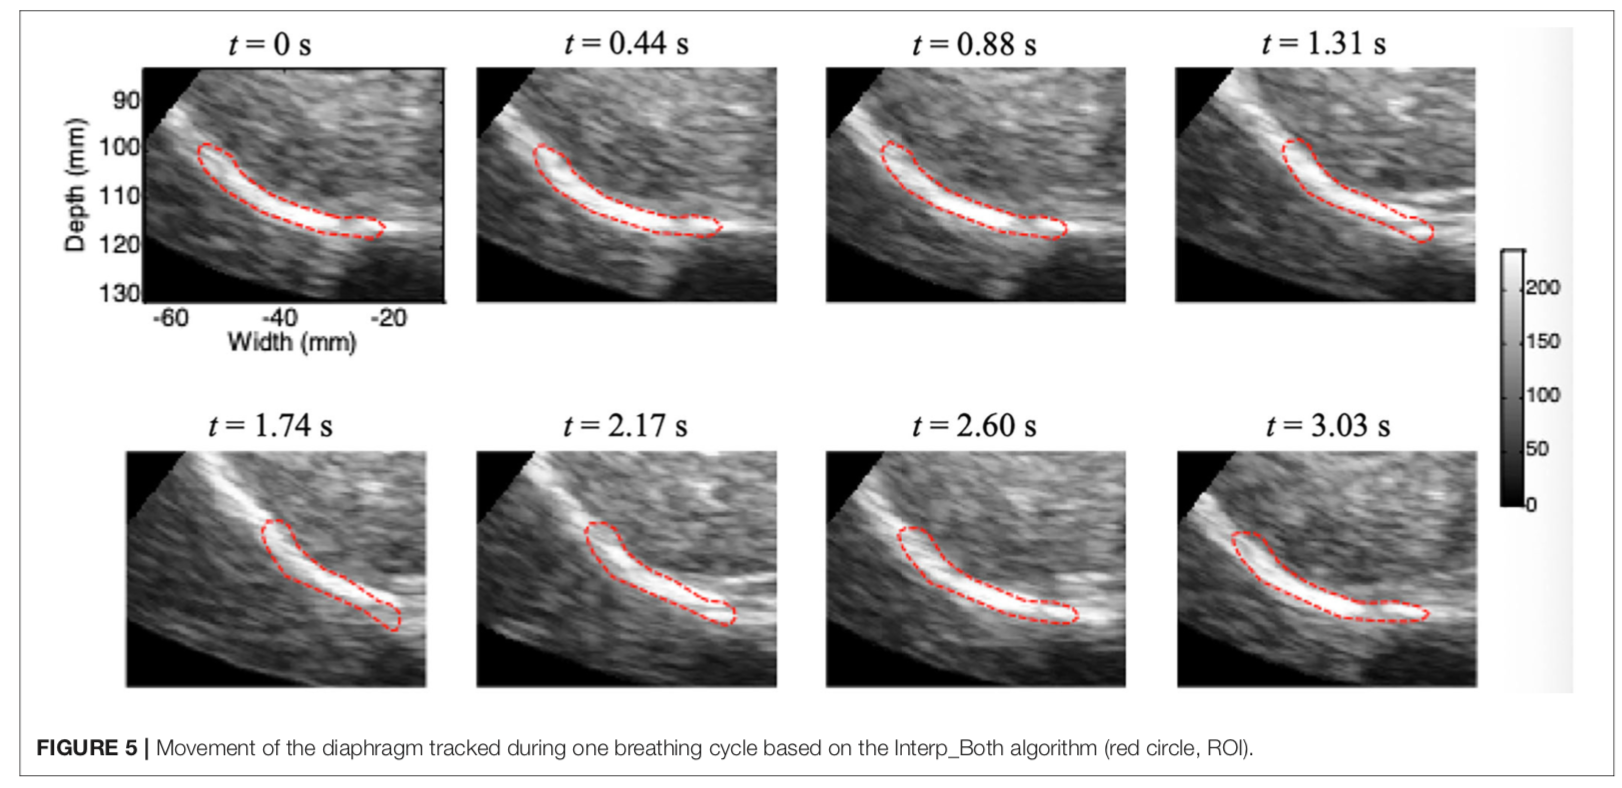

叶熊博士潜心于教学和自然科学研究,不忘初心、默默耕耘。分别主持厅局级和省部级项目各1项,校级项目3项,总资助经费30万元,发表第一作者SCI论文3篇,累计影响因子11.133分。于2017年10月,在《Int J Chron Obstruct Pulmon Dis》杂志(IF:3.355)发表题为“Echo intensity of the rectus femoris in stable COPD patients”的研究论文1篇,该研究探索了一种超声图像回声强度定量方法,用于评估慢性阻塞性肺病患者股四头肌功能,有助于早期诊断慢性阻塞性肺病患者的骨骼肌功能失调;于2021年5月,在《Frontiers in Medicine》杂志(IF:5.091)发表题为“A Novel Normalized Cross-Correlation Speckle-Tracking Ultrasound Algorithm for the Evaluation of Diaphragm Deformation”的研究论文1篇,该研究首次把互相关归一算法用于膈肌超声斑点追踪,为研究膈肌动力学提供了一种创新性的方法。该成果是叶熊老师和清华大学生物工程系罗建文研究员团队合作的阶段性成果